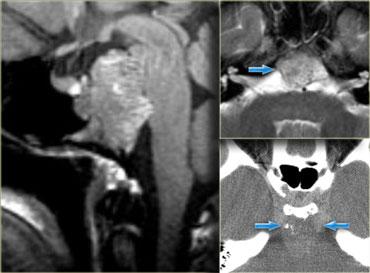

Sọ hầu u (Craniopharyngioma)

Sọ hầu u là bệnh lý thứ ba trong số ba bệnh lý có nguồn gốc từ biểu mô khe Rathke.

Về mặt kỹ thuật, đây là các khối u lành tính, nhưng khác với nang khe Rathke, chúng có thành dày và xâm lấn tại chỗ.

Về đại thể, đây là một khối phức tạp với nhiều nốt ở nền não, len lỏi dọc theo các khe não.

Thông thường, khối u không thể được cắt bỏ hoàn toàn.

Hình ảnh bên phải cho thấy một nang thành dày là một phần của sọ hầu u.

Trong hơn 50% trường hợp, sọ hầu u có hình ảnh đặc trưng bệnh lý (pathognomonic).

Trên các hình ảnh chuỗi xung T1W mặt phẳng đứng dọc không và có tiêm thuốc tương phản từ, có thể nhận thấy tuyến yên bị chèn ép.

Có một khối lớn trong hố yên và trên hố yên với các thành phần dạng nang, thành phần ngấm thuốc cũng như vôi hóa.

Các dấu hiệu này ở trẻ em gần như là đặc trưng bệnh lý của sọ hầu u (có thể chỉ cần chẩn đoán phân biệt với u bì – dermoid).

Hình ảnh mặt phẳng đứng ngang (coronal) của cùng một khối.

Và hình ảnh mặt phẳng ngang (axial).

CT không tiêm thuốc cản quang cho thấy các vôi hóa rõ ràng hơn.

Sau khi tiêm thuốc cản quang tĩnh mạch, toàn bộ phạm vi của tổn thương và các thành phần dạng nang của nó trở nên kém rõ ràng hơn nhiều.